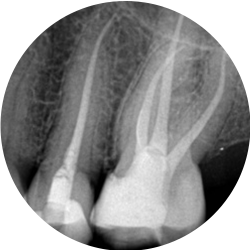

Yes sometimes endodontic treatments are not successful for a multitude of reasons and have to be redone.

A careful assessment will be made of your tooth to see if retreatment is the best option for you. Sometimes teeth have other more significant problems that may have a significant impact on the success of the retreatment and in these cases the tooth may have to be removed.

Most endodontically treated posterior teeth require restoration with a crown on completion of treatment. In some instances crown placement is delayed to assess the success of the endodontic treatment. Covering the tooth with a cast restoration significantly increases its long term survival.

If the tooth is already restored with a crown prior to treatment then it maybe possible to treat the tooth through the existing restoration.